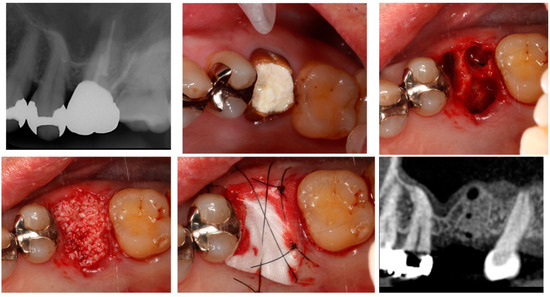

4.2. Alveolar Ridge Augmentation (Vertical/Horizontal)

4.2.1. Relationship between Alveolar Ridge Augmentation, Complications, and Early Failure

4.2.2. Selection of Bone Graft Material for Alveolar Ridge Augmentation